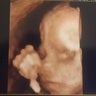

Medical / Health Care / Pharmaceuticals

Medico Serums C.S Bellavista 2013-2014 Medico Ocupacional 2013-2014